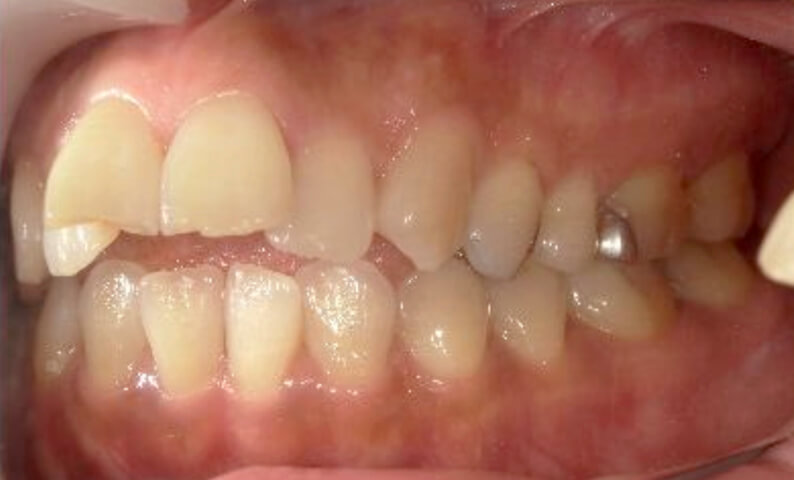

症例_003 上下顎の部分矯正

治療期間:12ヶ月金額:54万円+税男性八重歯前歯のガタガタ